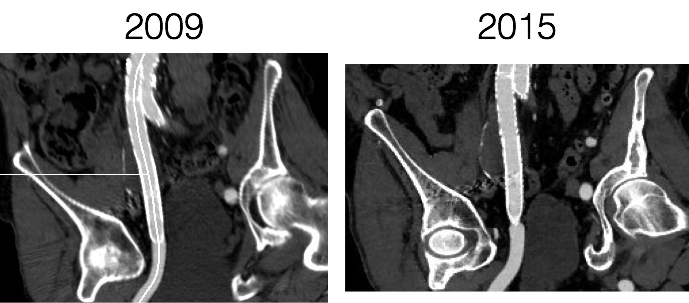

Never Stop Following Stent Grafts -Type IV endoleak causing slow growth in 12 year old stent graft

Centerline

The patient had undergone EVAR for bilateral common iliac artery aneurysm with the original Gore Excluder stent graft a dozen years before with coil embolization and extension to the external iliac on the larger side and femoral to internal iliac artery bypass on the other side. A coagulopathy, one of the clotting factor deficiencies, had made him high risk for bleeding with major open surgery. His aneurysms never shrank but remained stable and without visible endoleak by CT for a long time resulting in ever longer intervals between followup.

2013_1

2013

Between 2009 and 2013, there was subtle enlargement on the embolized side without a type I or type III leak, and the patient was brought back a year and a half later, with further growth of the sac.

1-2015_3

2015

This was a relatively rare type IV endoleak that was causing sac enlargement due to excessive graft porosity of the original Excluder’s graft material. Its treatment is either explantation or relining. We chose to reline the graft with an Excluder aortic cuff at the top and two Excluder iliac limbs.

2015-11-26 13_25_23

This was done percutaneously and in short followup, there has been stabilization and even some reduction in the aneurysm circumference.